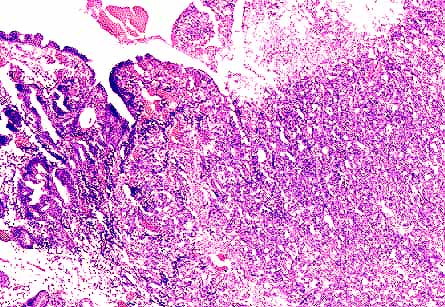

Foto nº 2: Carcinoma pobremente diferenciado en relación con la mucosa gástrica antral.

Foto nº 4: Área de patrón hepatoide. Se puede apreciar una tendencia a la disposición trabecular.